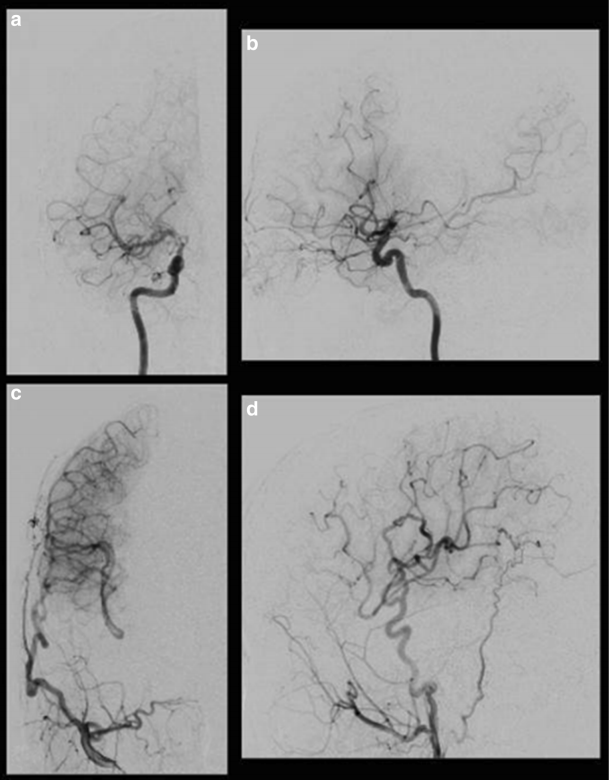

MRI未发现脑卒中病灶,但基底节区有多处血流空洞。MRA显示右侧颈内动脉终末段狭窄。左侧颈内动脉造影未见颈内动脉狭窄,右侧大脑前动脉由左侧大脑前动脉经前连合动脉供应。右颈内动脉血管摄影显示终端的狭窄部分颈内动脉和大脑前动脉(图1)。大脑中动脉比左边膨胀(图1)。烟雾血管出现在颈内动脉的顶部(图1)。与左侧相比,右侧大脑中动脉区摄取无明显下降(图2)。

图1:术前右颈动脉造影显示IC末端顶端烟雾血管发展,MCA扩张

术后5天、7个月MRI未见缺血性病变。在MRA的7个月内,STA似乎有发展和扩大。选择性右侧颈外动脉血管造影显示,经右侧STA可向右侧MCA区供血较多(图3)。

图3:术后右颈动脉血管造影显示右脑外动脉旁路血流通过MCA和ACA供应灌注较少区域。右侧颈内动脉正、侧位(a)。右颈外动脉正、侧位(c)